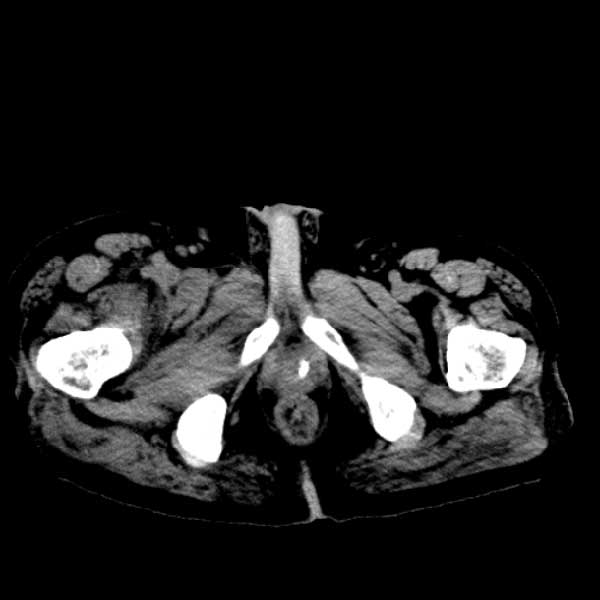

标题: CT13513:男 71 腹部疼痛20余天,近几天高热就诊,骨窗未见异 [打印本页]

标题: CT13513:男 71 腹部疼痛20余天,近几天高热就诊,骨窗未见异

考虑感染性病变可能性大,起源于阑尾?

感染,脓肿形成

考虑为化脓性阑尾炎.脓肿形成.及多肌肉累及.

考虑右侧腰大肌脓肿,向右髂窝、右腹股沟流注。

支持化脓性阑尾炎伴右髂窝脓肿、腰大肌腰方肌脓肿形成。

考虑腹腔及盆腔化脓性炎症,累及右侧髋关节及腹股沟区.

首先考虑化脓性阑尾炎伴腰大肌、腰方肌脓肿,不除外回盲部结核。

回盲部癌待排除。

患者肠镜检查考虑结肠癌,病理证实

患者肠镜检查考虑结肠癌,病理证实。肺部ct可见多发结节,考虑转移